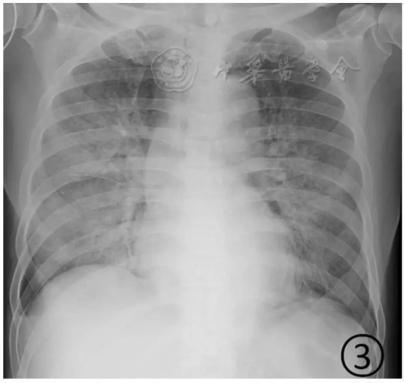

按照国家卫健委发布的新型冠状病毒肺炎试行第六版诊疗方案之中的临床分型,新冠肺炎分为轻型、普通型、重型及危重型。在患者的肺部CT中,轻型者没有比较明显的肺炎改变;普通型者以肺部出现局限性斑片状或很多节段性片状“病灶”为主(图②);重型者双肺可出现较多的白色小斑片“病灶”,部分融合成大片状“病灶”(图③);危重型者会有“白肺”表现(图④)。

▲从上到下依次为普通型、重型及危重型新冠肺炎患者的肺部CT表现(图片来自网络)